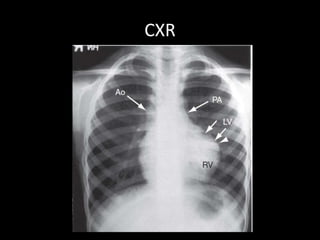

CXR

• Reduced PBF markings

• Lacy appearance in

Pulmonary Atresia

• Dilated Asc Ao

• Rt Ao arch 20-30%

• Coer-en-Sabot

• Heart resembling a

wooden boot

– Concave PA bay

– Small underfilled LV

above a horizontal IVS

– Concentric RVH

• Intrauterine life LV is

normal – so boot shape

develops after 1-2 mos

of birth

• TOF-PA – Boot even in

neonates if low PBF